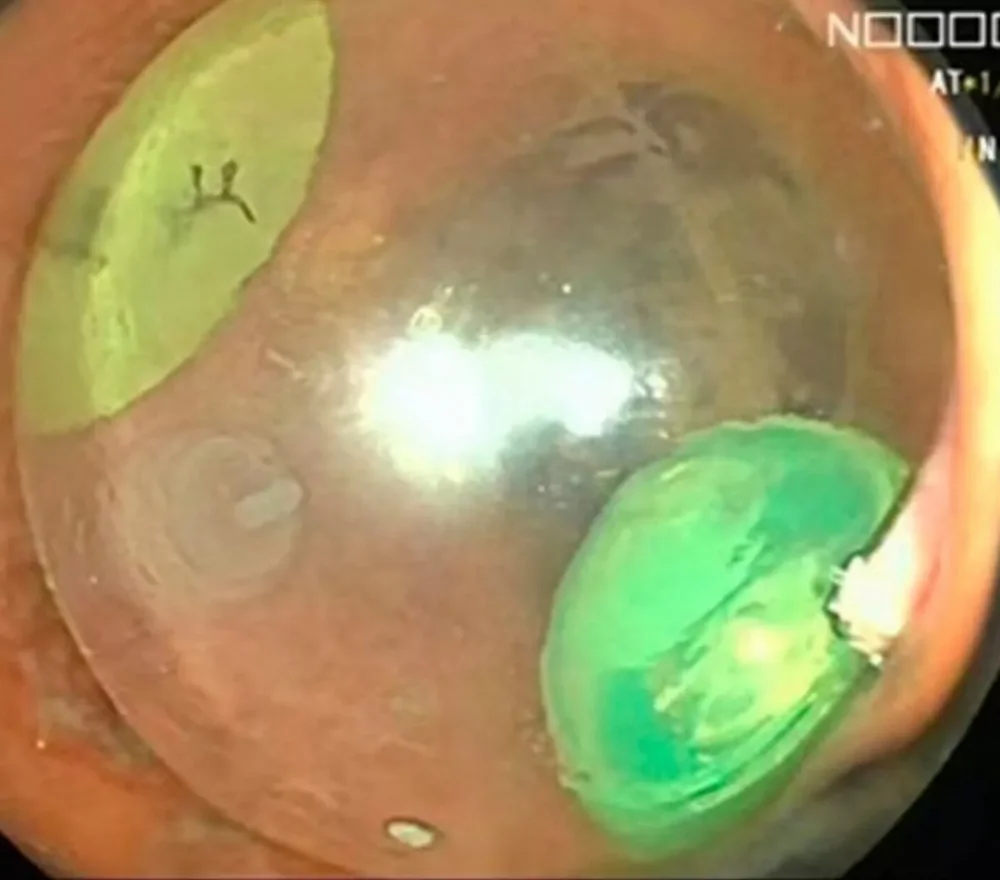

Врачи убедились, что в прямой кишке пациента, примерно в 7 сантиметрах от его заднего прохода, застрял круглый инородный предмет диаметром около 6,5 сантиметров. Это была прозрачная сфера, частично наполненная красной жидкостью, на боках которой красовались мультяшные личики.

Чтобы извлечь шарик, хирурги придумали хитроумный план, максимально облегчающий их работу. Они поместили пациента под общий наркоз, а затем с помощью скальпеля проткнули эластичный шарик. Вся жидкость из шарика вытекла, а общий размер игрушки уменьшился из-за выхода воздуха. Затем шар был успешно удален с помощью щипцов и специального зажима через прямую кишку мужчины.